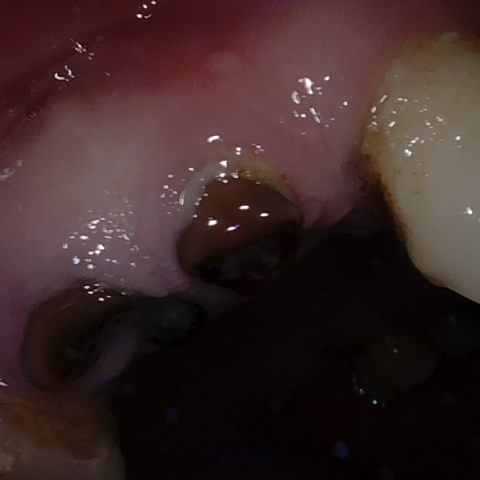

Annotated as "Good"